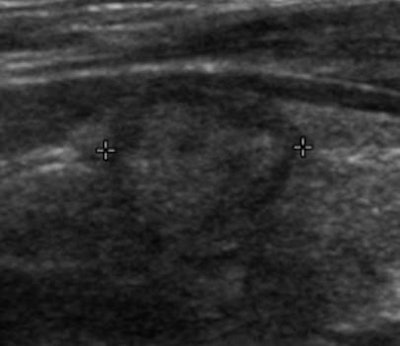

Of the 2,090 thyroid surgery patients included in the study, 680 were found to have thyroid cancer; 101 (15%) had incidental thyroid nodules detected on imaging. After the researchers applied the SRU recommendations to the 90 patients who had available ultrasound images or reports, they determined that 16 (18% of the 90 patients and 2% of all thyroid cancers) would have been missed using the criteria.

The tumors that would not have been worked up under the SRU criteria had a mean size of 1.1 cm (range, 0.9-1.4 cm), compared with a mean size of 2.5 cm (range, 1.0-7.6 cm) for those that had met the SRU recommendations. The difference was statistically significant (p < 0.001). Nearly all (15/16, 94%) were stage I, compared with 47 (64%) of the 74 incidental thyroid nodules that met the SRU criteria.

Fourteen (88%) of the 16 SRU criteria-negative cancers were papillary carcinoma; small papillary carcinoma has an extremely high survival rate. The other cases were a follicular carcinoma and a medullary carcinoma.